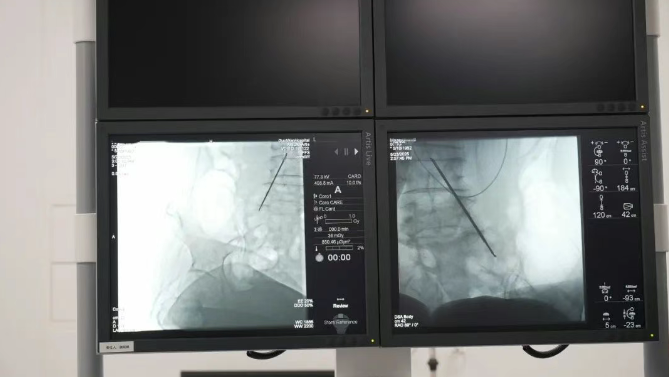

精準靶向,直擊疼痛根源鞘內(nèi)泵植入技術(shù)通過微創(chuàng)手段,將一枚微型鎮(zhèn)痛泵植入體內(nèi),經(jīng)導管精準連接至脊髓蛛網(wǎng)膜下腔(鞘內(nèi))。這一“生物鎮(zhèn)痛開關(guān)”可直接將鎮(zhèn)痛藥物輸送至中樞神經(jīng)系統(tǒng),相較傳統(tǒng)口服或靜脈給藥,所需藥量僅為1/300,卻能實現(xiàn)更高效、更精準的疼痛控制,從根源阻斷疼痛信號傳導,讓患者徹底擺脫疼痛困擾。